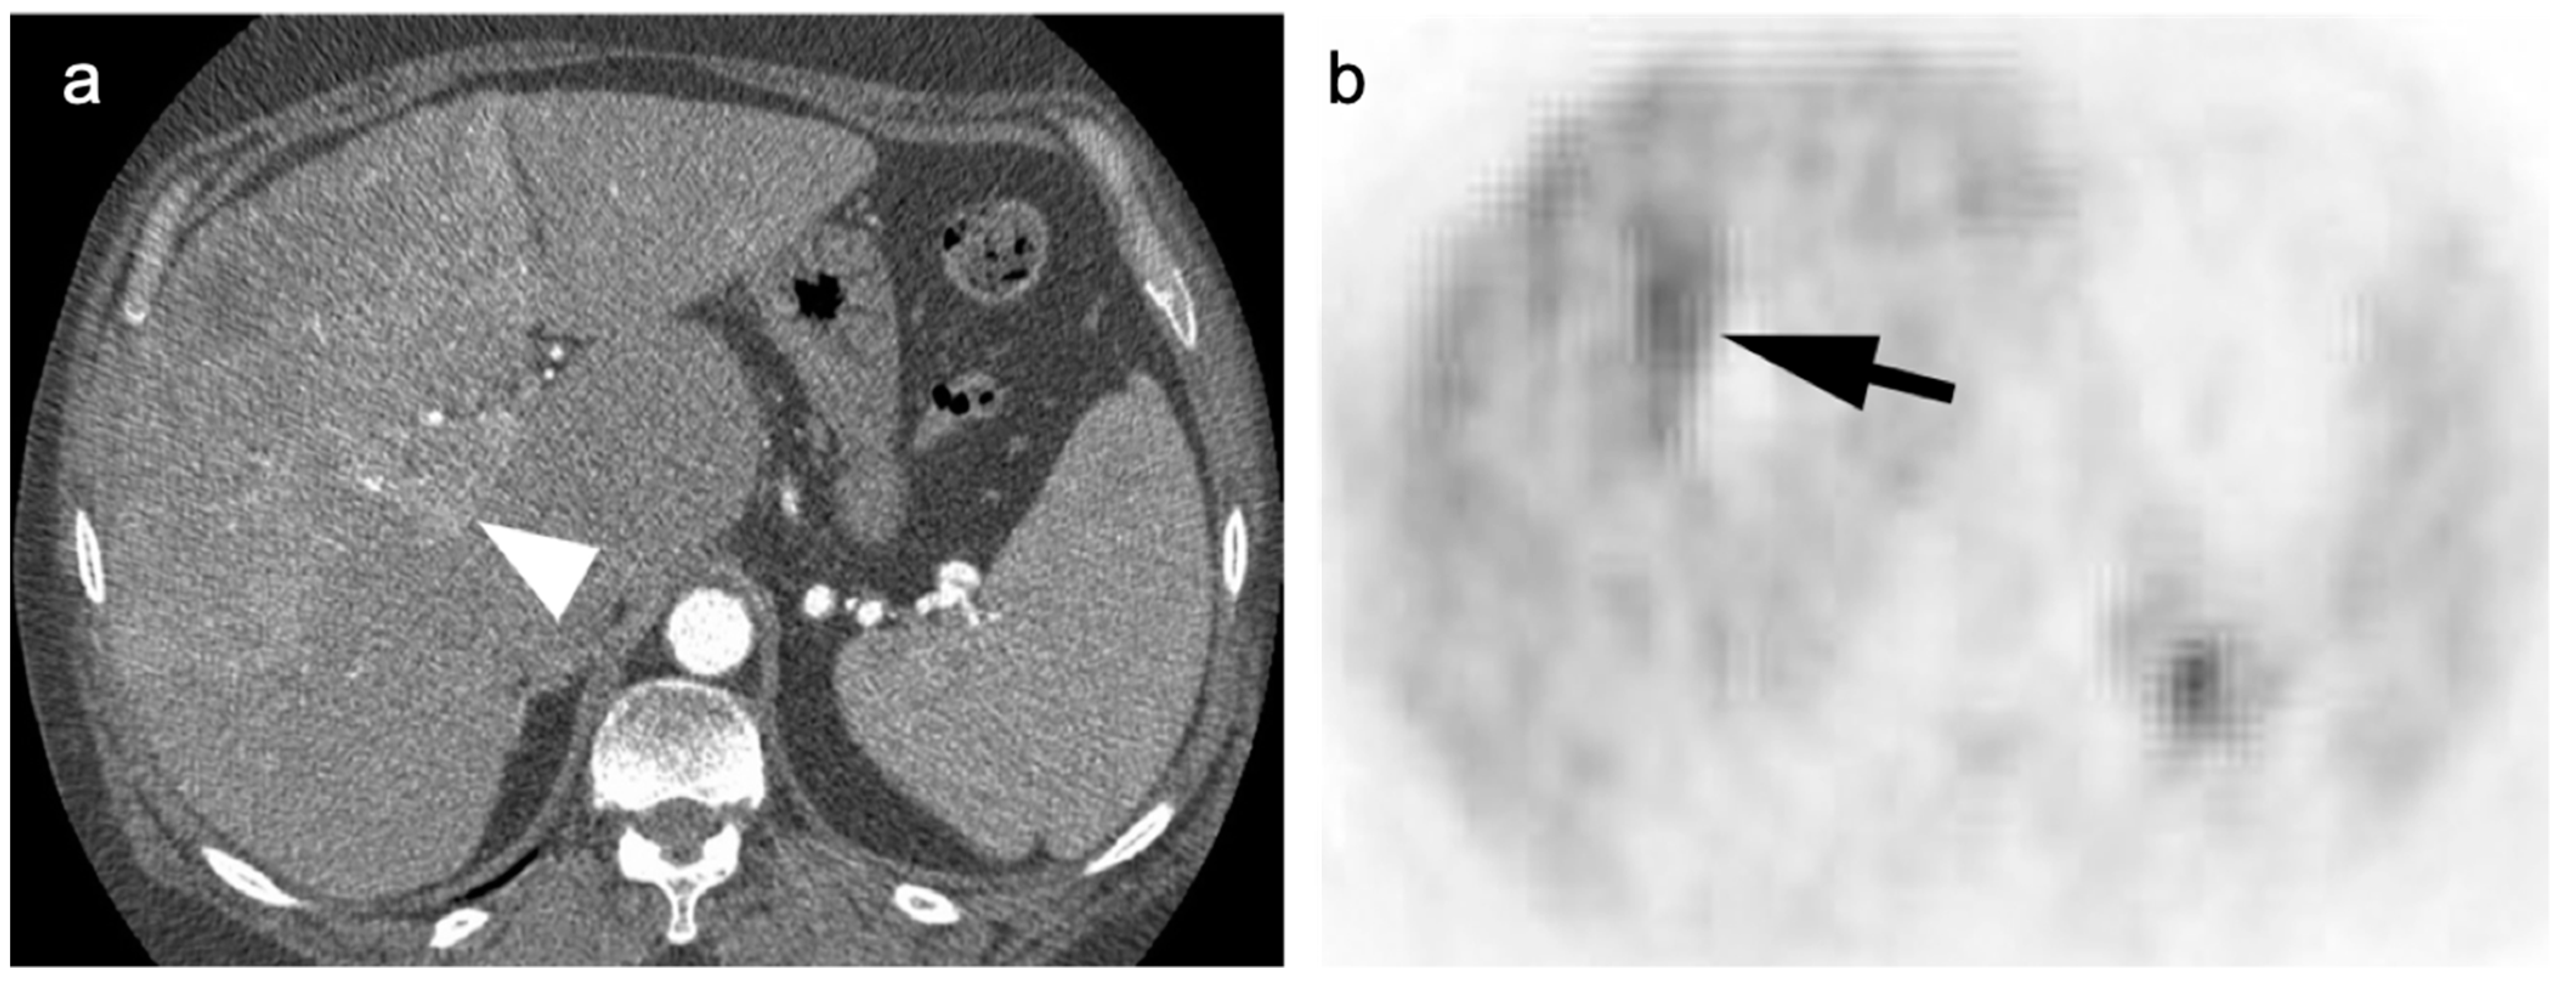

- Kluge, R.; Schmidt, F.; Caca, K.; Barthel, H.; Hesse, S.; Georgi, P.; Seese, A.; Huster, D.; Berr, F. Positron emission tomography with [18F]fluoro-2-deoxy-D-glucose for diagnosis and staging of bile duct cancer. Hepatology 2001, 33, 1029–1035. [Google Scholar] [CrossRef]

- Kim, J.Y.; Kim, M.-H.; Lee, T.Y.; Hwang, C.Y.; Kim, J.S.; Yun, S.-C.; Lee, S.S.; Seo, D.W.; Lee, S.K. Clinical Role of 18F-FDG PET-CT in Suspected and Potentially Operable Cholangiocarcinoma: A Prospective Study Compared with Conventional Imaging. Am. J. Gastroenterol. 2008, 103, 1145–1151. [Google Scholar] [CrossRef]

- Fong, Z.V.; Brownlee, S.A.; Qadan, M.; Tanabe, K.K. The Clinical Management of Cholangiocarcinoma in the United States and Europe: A Comprehensive and Evidence-Based Comparison of Guidelines. Ann. Surg. Oncol. 2021, 28, 2660–2674. [Google Scholar] [CrossRef]

- Kiefer, L.S.; Sekler, J.; Gückel, B.; Kraus, M.S.; la Fougère, C.; Nikolaou, K.; Bitzer, M.; Gatidis, S.; Pfannenberg, C. Impact of 18F-FDG-PET/CT on Clinical Management in Patients with Cholangiocellular Carcinoma. BJR Open 2021, 3, 20210008. [Google Scholar] [CrossRef] [PubMed]